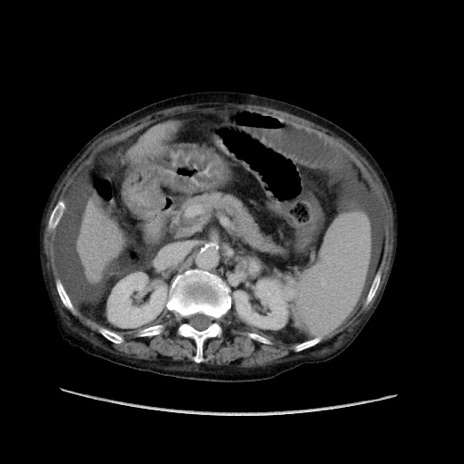

症例31(横断像)

【症例】80歳代 女性

【主訴】腹部膨満感

【現病歴】他院にて肝硬変にてフォロー中。1週間前から便秘、腹部膨満感、臍部腫瘤あり受診となる。

【既往歴】肝硬変

【身体所見】腹部膨隆あり、皮膚変化なし、疼痛なし。

【データ】WBC 4600、CRP 0.25